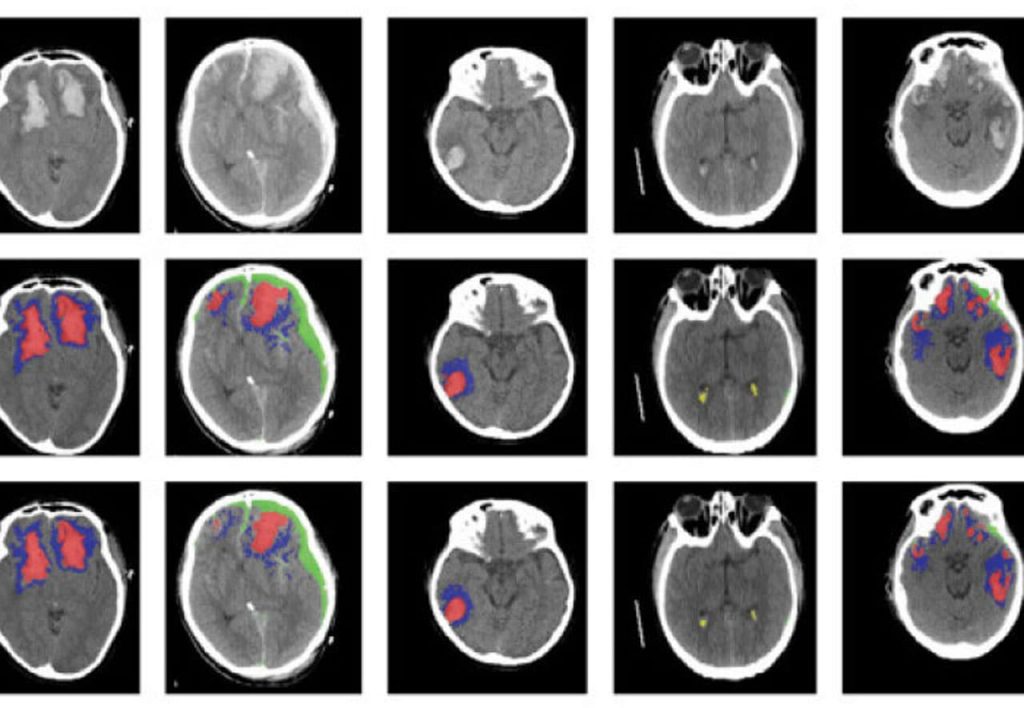

U saradnji sa Univerzitetom Kembridža, naučnici na Imperijalnog kodedža London su pronašli algoritam vještačke inteligencije (VI) za prepoznavanje različitih tipova povreda mozga. Osim toga, ovaj algoritam može da: otkrije, raščlani, izmjeri i napravi razliku između vrsta lezija mozga, koristeći slike računarske tomografije (engl. computer tomography – CT).

Pripremali su alat na više od 600 raznolikih skeniranja CT-a, na kojima su moždane povrede raznih veličina i vrsta, prije nego što su provjerili alat na ogromnom skupu podataka skeniranja CT-a.